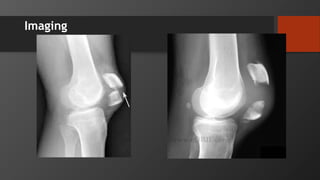

Imaging

Imaging – bipartite patella